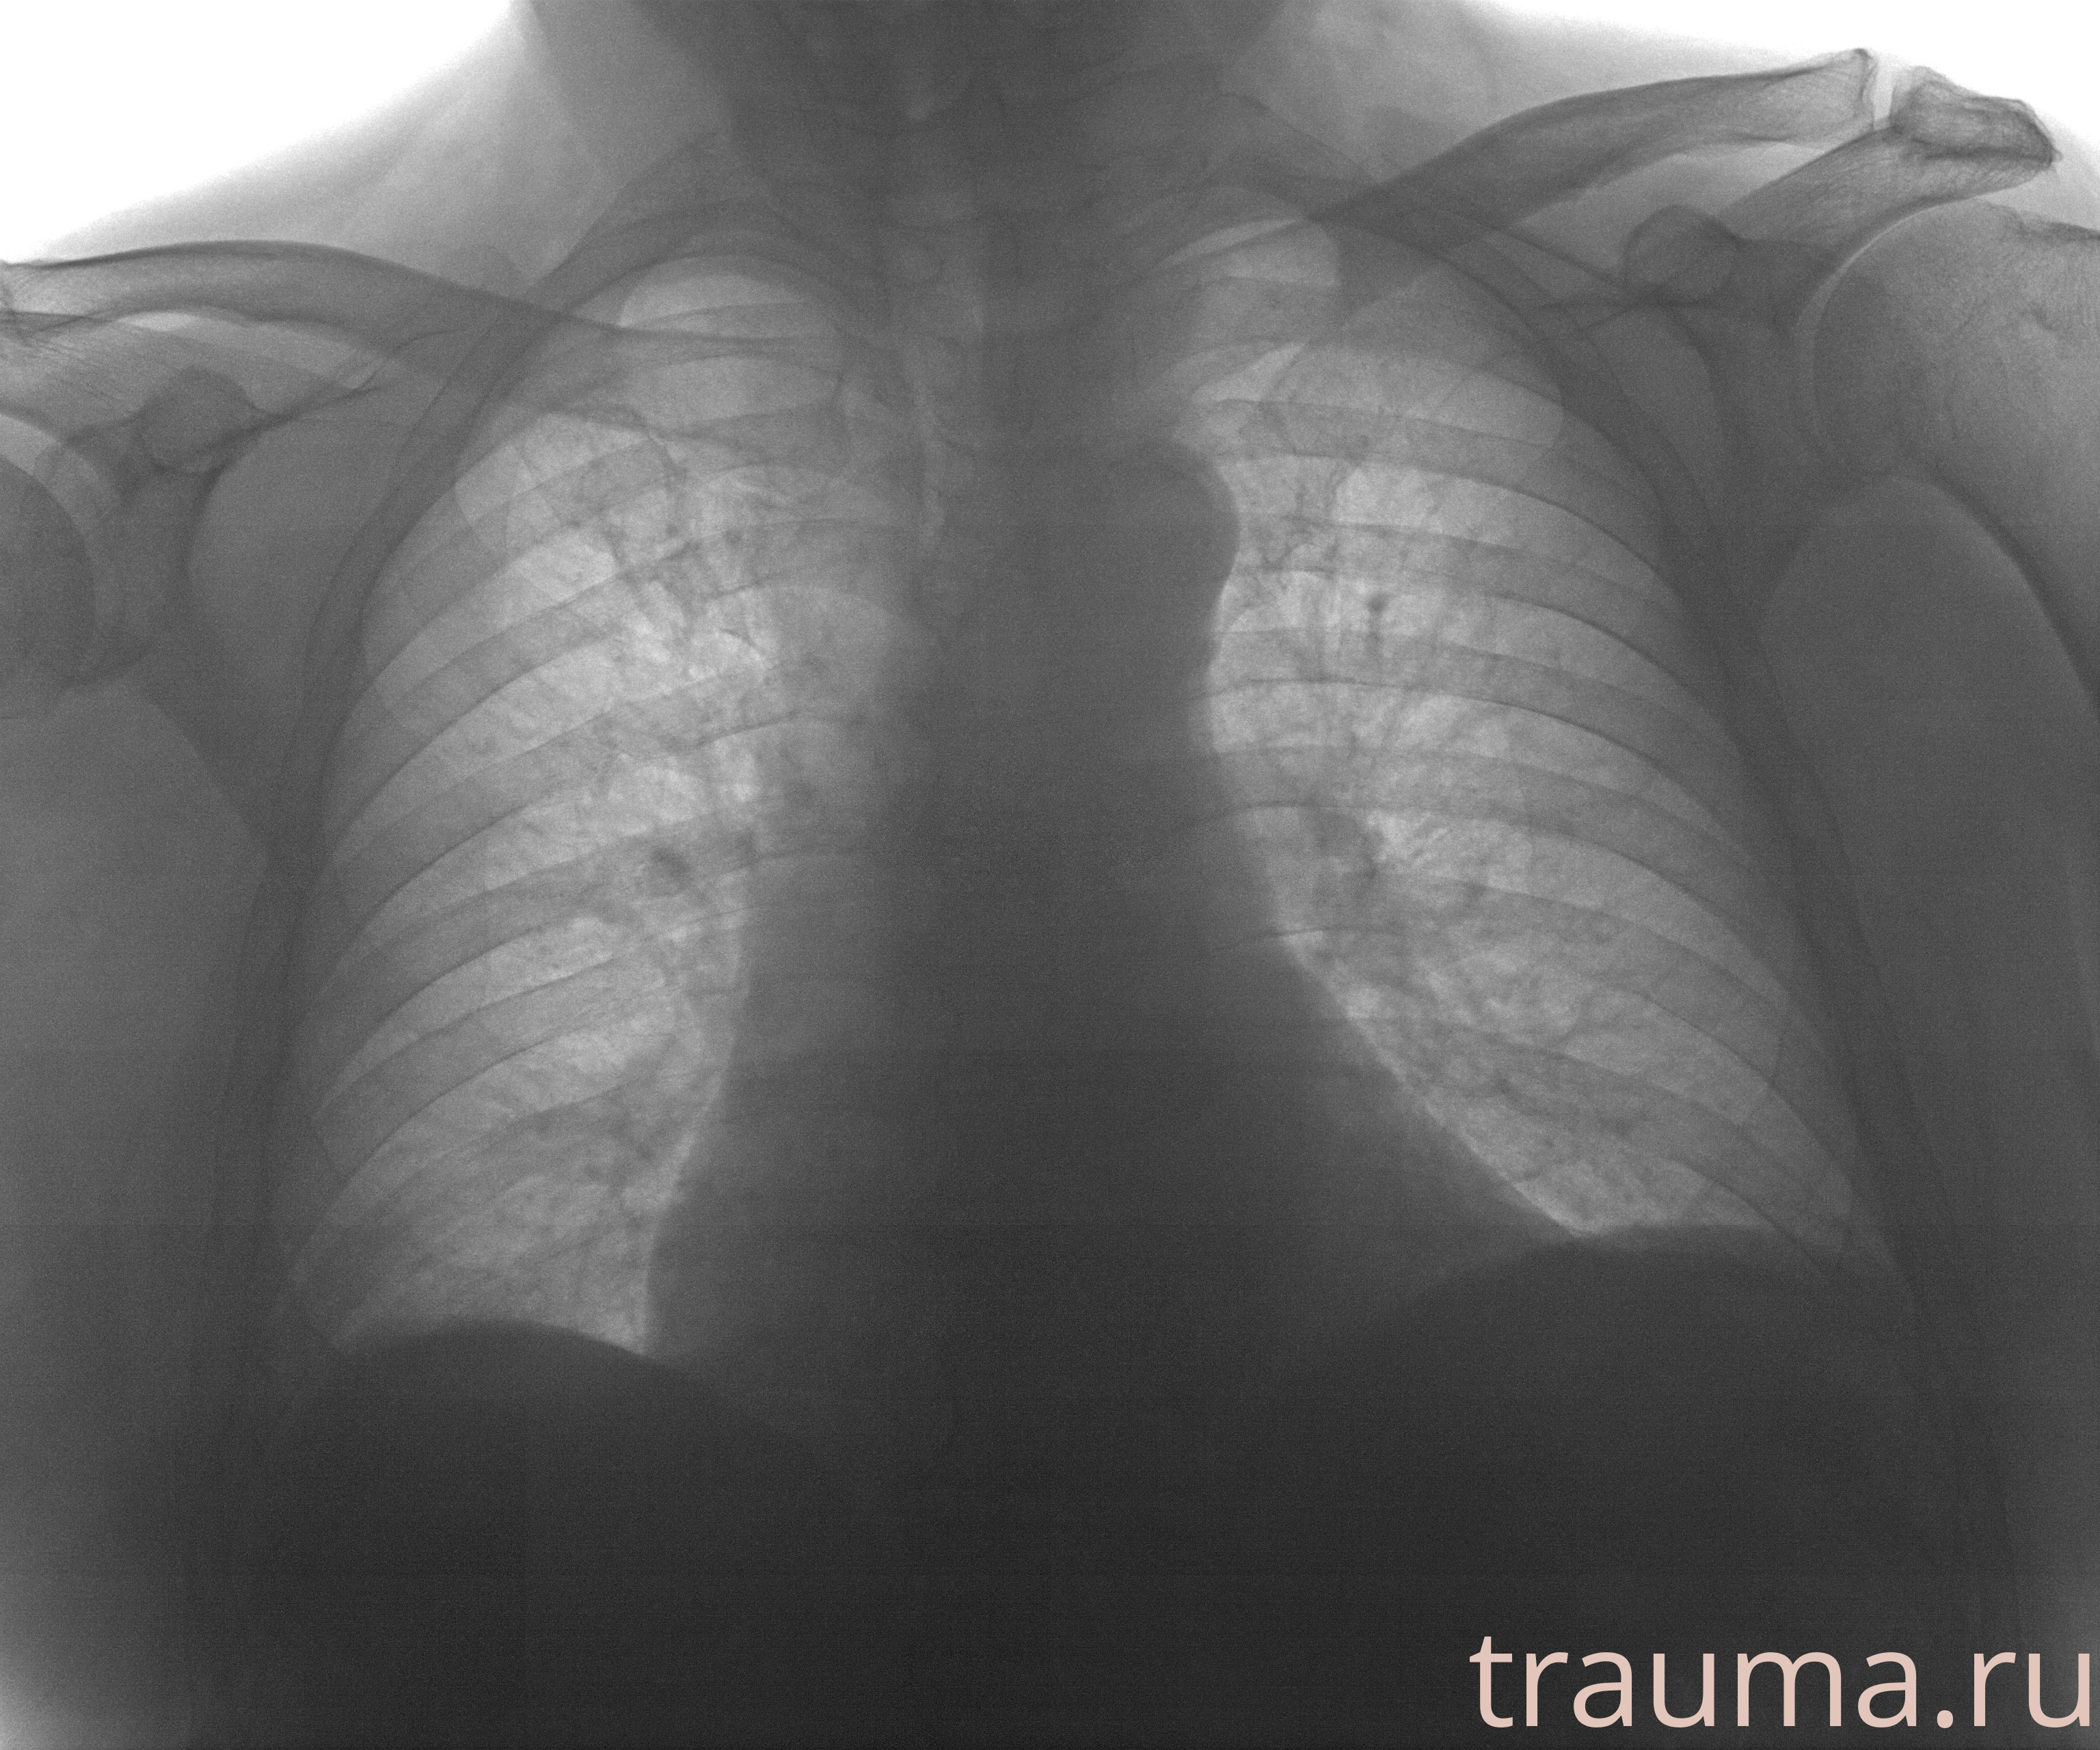

Рентген на дому: по вашему адресу приезжает врач-рентгенолог, травматолог-ортопед с мобильным рентгеновским аппаратом, проводит диагностику травмы или заболевания, делает необходимые рентгенограммы, дает рекомендации по дальнейшему лечению. Получить качественные снимки в домашних условиях возможно благодаря уникальной методике, разработанной МосРентген Центром для института  Склифосовского

при переломе шейки бедра и пневмонии от компании МосРентген Центр - партнера Института имени Склифосовского